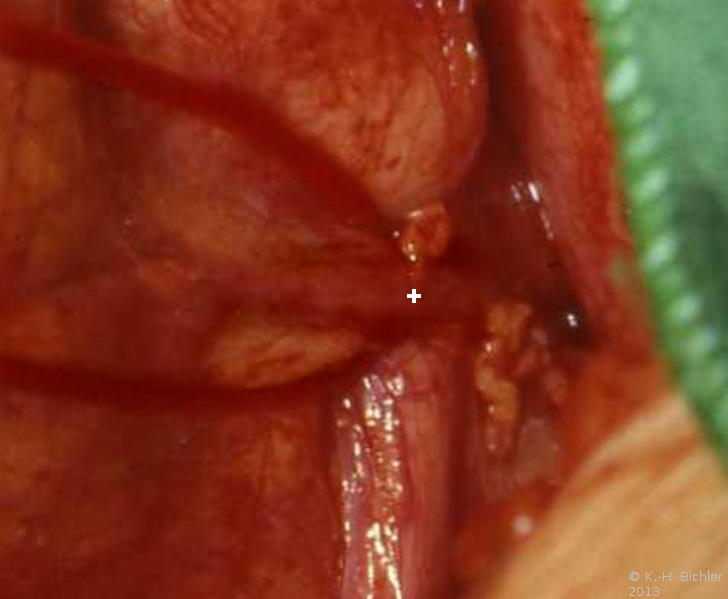

Bei dem 8-jährigen Jungen waren Schmerzen im linken Oberbauch sowie rezidivierende Harnwegsinfekte Ursachen für die Abklärung. sonographisch und röntgenologisch fanden sich Nierenkelchkonkremente in einer Harnstaaungsniere (Abbildungen 21,22,23). Bei der retrograden Sondierung ergab sich ein deutlicher Widerstand in Höhe des Ureterabgangs. Die Freilegung zeigte eine aberrierende Arterie als Abflusshindernis. Nach Durchtrennung des Harnleiters Eröffnung des Nierenbeckens zur Steinentfernung und Abgangsplastik des vorgelagerten Harnleiters. Normalisierung der Abflussverhältnisse.